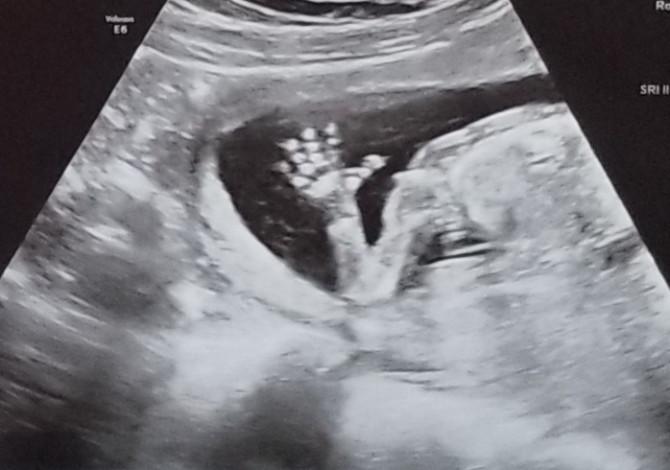

“我们很担心因为我特殊的子宫,医生们能否为我的具体情况提供足够的产前护理,直到第9周的超声波扫描,我看到了宝宝健康的心跳,我才真正有了希望。”